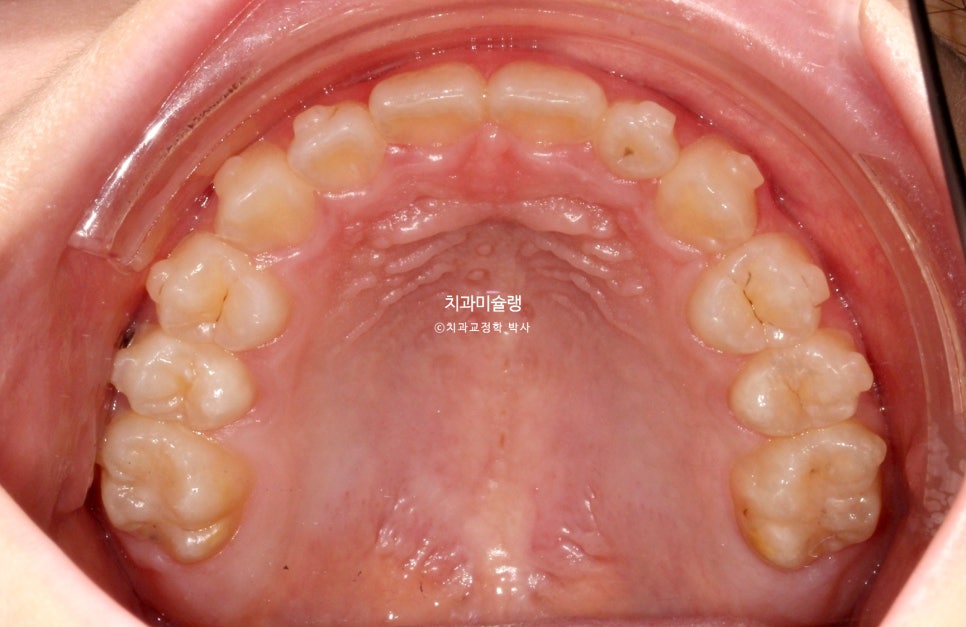

24년 6월, 교정치료를 위해 내원한 만 10세 어린이 입니다.

송곳니 덧니와 개방교합이 보입니다.

고치고 싶은것은 ‘덧니’ 입니다.

위 앞니가 아래 앞니를 덮지 못하고 아래 앞니가 더 앞으로 나가있는 반대교합 입니다.

안모에서는 아래턱이 발달한 주걱턱 양상이 보입니다.

주걱턱의 의학적 정식 명칭은 골격성 3급 부정교합 이라고 합니다.